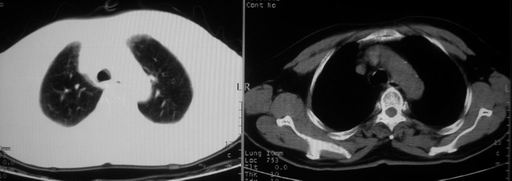

男,78岁,咳嗽、咳痰、发热入院,抗炎治疗一周后已退热,咳血似痰。

10月9日片: